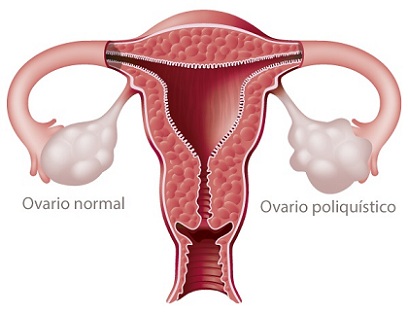

Una joven pareja originaria de Georgia, sabía que tenía muy pocas probabilidades de tener un hijo, pues Ashley Zachmeyer de 22 años tenía una condición conocida como Síndrome de varios poliquísticos, un grave problema que es muy común en las mujeres y se origina debido a un desorden hormonal ocasionando en la mayoría de los casos problemas de infertilidad, sangrado uterino abundante y abortos espontáneos.

Su Síndrome podría en cualquier momento ocasionar un aborto espontáneo, era una probabilidad muy alta.